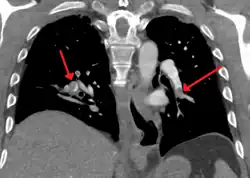

CT pulmonary angiography

CT pulmonary angiography (CTPA) is a pulmonary angiogram obtained using computed tomography (CT) with radiocontrast rather than right heart catheterization. Its advantages are that it is accurate, it is non-invasive, it is more often available, and it may identify other lung disorders in case there is no pulmonary embolism. The accuracy and non-invasive nature of CTPA also make it advantageous for people who are pregnant.[61]

Assessing the accuracy of CT pulmonary angiography is hindered by the rapid changes in the number of rows of detectors available in multidetector CT (MDCT) machines.[62] According to a cohort study, single-slice spiral CT may help diagnose detection among people with suspected pulmonary embolism.[63] In this study, the sensitivity was 69% and specificity was 84%. In this study which had a prevalence of detection was 32%, the positive predictive value of 67.0% and negative predictive value of 85.2%. However, this study's results may be biased due to possible incorporation bias, since the CT scan was the final diagnostic tool in people with pulmonary embolism. The authors noted that a negative single-slice CT scan is insufficient to rule out pulmonary embolism on its own. A separate study with a mixture of 4-slice and 16-slice scanners reported a sensitivity of 83% and a specificity of 96%, which means that it is a good test for ruling out a pulmonary embolism if it is not seen on imaging and that it is very good at confirming a pulmonary embolism is present if it is seen. This study noted that additional testing is necessary when the clinical probability is inconsistent with the imaging results.[64] CTPA is non-inferior to VQ scanning, and identifies more emboli (without necessarily improving the outcome) compared to VQ scanning.[65]